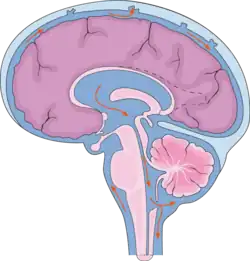

Спинномозгова́я жи́дкость, или ли́квор (лат. liquor cerebrospinalis[1]) — жидкость, постоянно циркулирующая в желудочках головного мозга, ликворопроводящих путях, субарахноидальном (подпаутинном) пространстве головного и спинного мозга[2].

Циркуляция

Ликвор образуется в мозге: в эпендимальных клетках сосудистого сплетения (50—70 %), вокруг кровеносных сосудов и вдоль желудочковой стенки. Далее цереброспинальная жидкость циркулирует от боковых желудочков в отверстие Монро (межжелудочковое отверстие), затем — вдоль третьего желудочка, проходит через Сильвиев водопровод. Затем проходит в четвёртый желудочек, через отверстия Мажанди и Лушки выходит в субарахноидальное пространство головного и спинного мозга. Ликвор реабсорбируется в кровь венозных синусов и через грануляции паутинной оболочки.